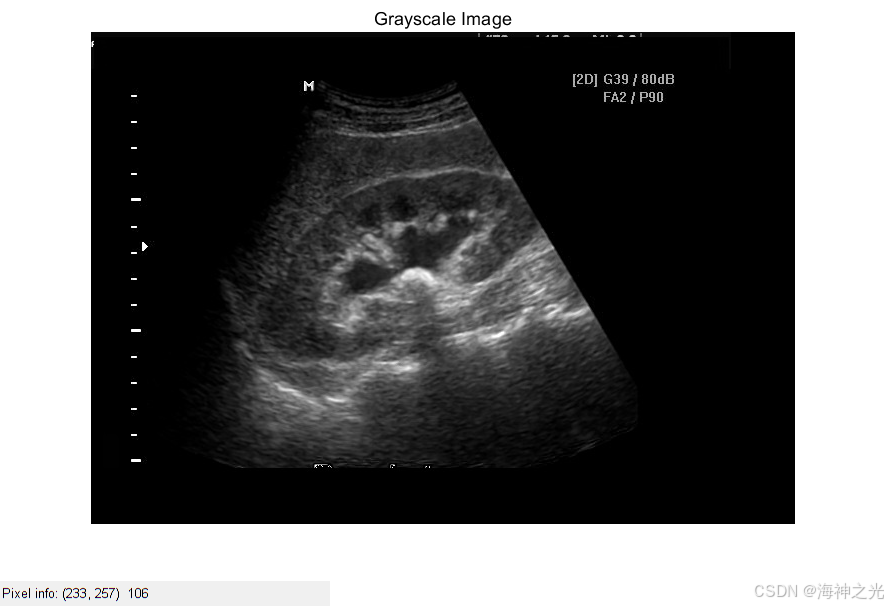

⛄三、运行结果